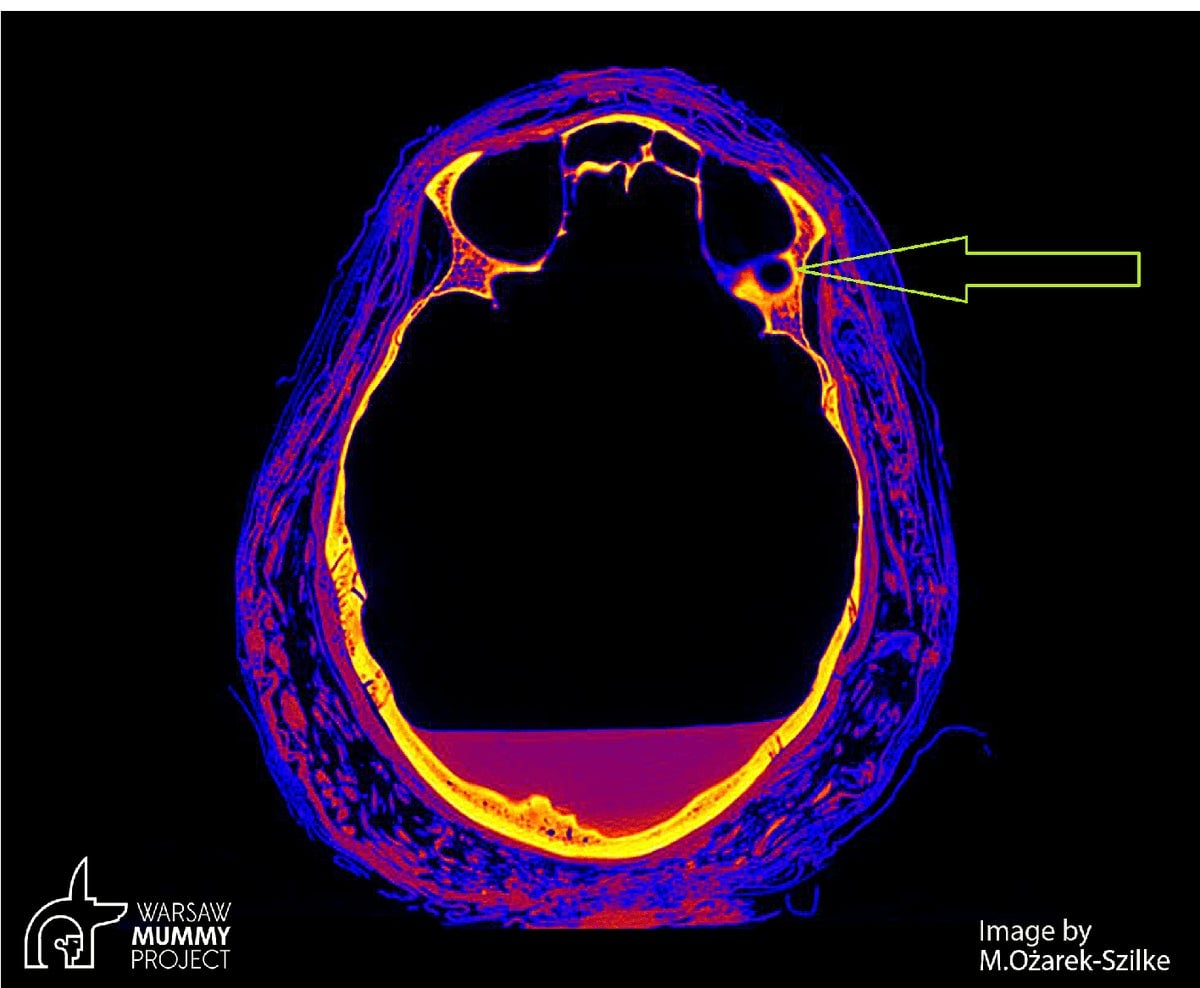

En las tomografías computarizadas se puede ver un pequeño cambio patológico, de unos 7 milímetros de diámetro, una lesión redonda que rodea un espacio vacío, en el hueso detrás de la órbita izquierda. Lo más probable es que se trate de un cambio causado por un tumor, posiblemente un sitio metastásico. Este tipo de cambios metastásicos en los huesos del cráneo se dan, entre otros, después de un adenoma, pero si fuera este tipo de tumor, las pruebas histopatológicas nos darían una respuesta definitiva. Además, hay grandes cavidades en los huesos de la cara, incluida la cavidad nasal, los senos maxilares y la parte palatina de los huesos maxilares. Los cambios en los huesos craneofaciales se corresponden con el cáncer nasofaríngeo en pacientes modernos.